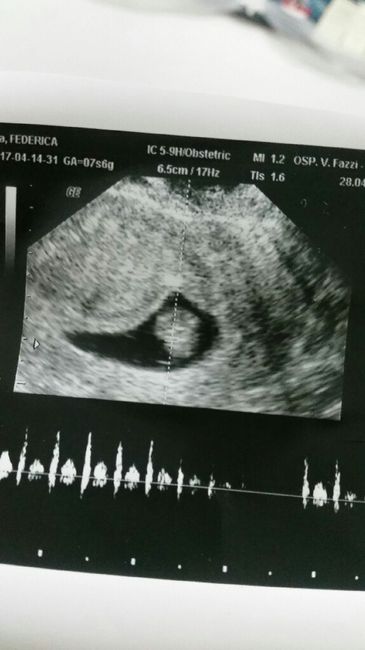

3272 giorni faChe emozione vita mia

3276 giorni faIeri per un mancamento mi hanno fatto un ecoPer la prima volta ho sentito il battito... Che emozione fortissima 150 battiti 😍😍😍😍😍